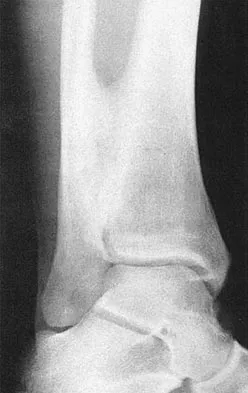

Figures 5a and 5b show axial and coronal MRI images of the left ankle of a patient with lateral ankle pain. What is the most likely diagnosis?

Explanation

The figures show a longitudinal split within the peroneus brevis tendon as it courses posterior to the fibula. The peroneus longus tendon has been driven between the medial and lateral components of the peroneus brevis tendon. Peroneal split syndrome is a cause of lateral ankle pain but may be less asymptomatic in the elderly. It may be associated with tendon subluxation following a tear of the superior peroneal retinaculum.